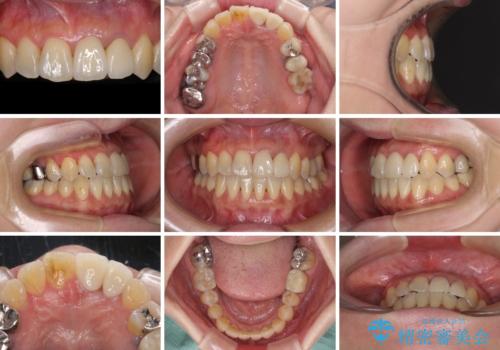

反対咬合で痛む前歯を改善 インビザラインによる矯正治療

骨格的に下顎が前方位にありますが、歯列矯正で前歯の被蓋関係を改善することができると判断されたため、インビザラインにより矯正治療を行うこととしました。

また、上顎前歯と下顎大臼歯に神経を取り除いた歯があったため、矯正治療後に、セラミッククラウンにて補綴することとしました。

前歯が内側に倒れ込む力がかかり、正常な歯ぎしりもできないため、非常に負担のかかりやすい咬み合わせでした。

矯正治療中に上顎前歯が下顎前歯を乗り越える際は、前歯でしか咬めない状況が続くため、食事など不便を感じましたが、治療後には前歯の痛みもなくなり、安定した咬み合わせとなりました。